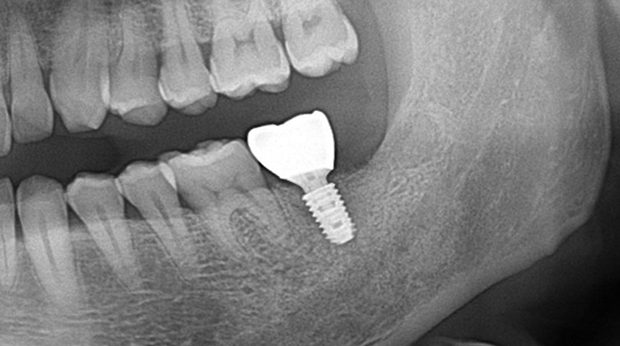

의식하진정법(수면마취)/임플란트

임플란트와 사랑니 발치는 외과적 시술로 잇몸을 절개하는 외과적 시술은

짧으면 짧을 수록 시술 후 붓기와 통증이 최소화됩니다.

치과의사 경력 14년차 구강외과 전문의가 빠르고 안전하게, 아프지 않게 수술해 드립니다.

치과경력 14년차 구강외과 전문의

연세대학교 치과대학 구강외과 임상 조교수